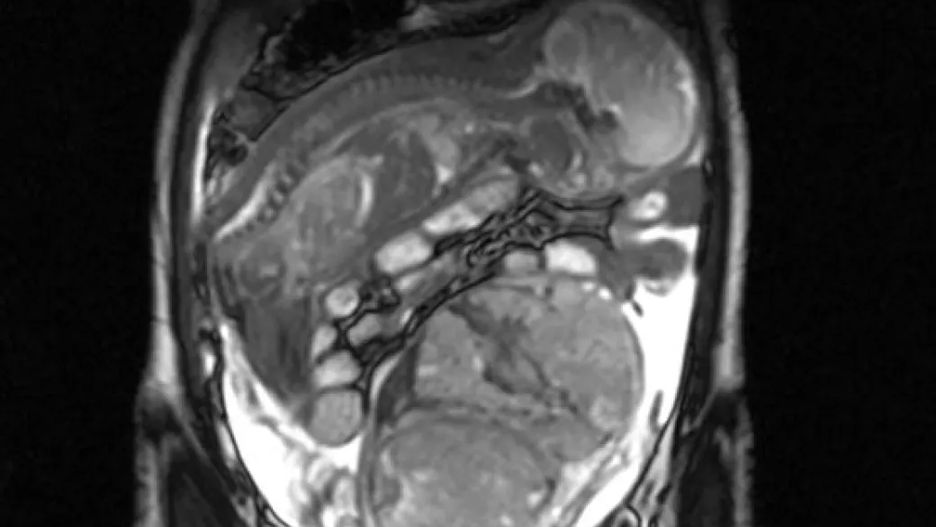

Lekarze odkryli również, że silne bóle brzucha są spowodowane tym, że podczas nieudanej próby przeprowadzenia aborcji doszło do pęknięcia macicy, a rozwijający się płód przedostał się w worku owodniowym do jelita. Niezwykłe zdjęcie z badania obrazowego obiegło media na całym świecie.

Płód rozwijał się w jelicie

Płód rozwijał się w jelicie © Facebook